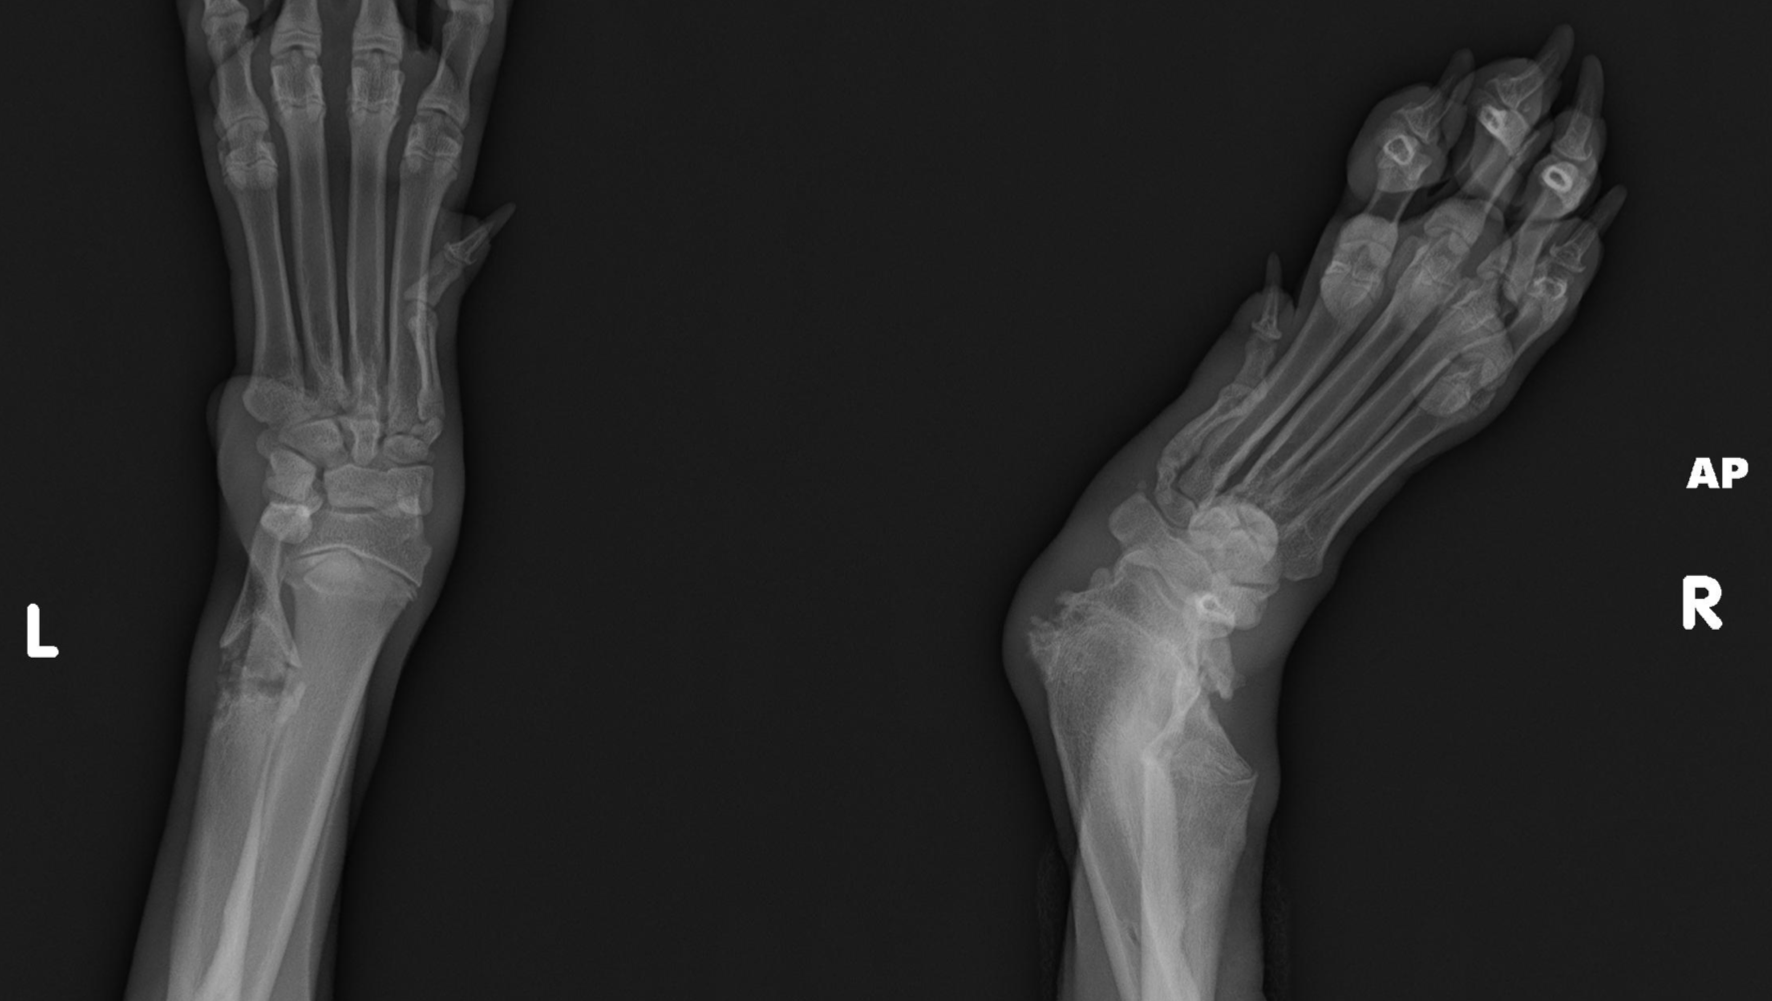

Ducky’s face and head were terribly swollen because of several skull fractures. She could not walk due to a broken hind leg, and badly deformed front limbs (partially a result of nutritional starvation). She had several broken ribs, and fractures throughout her body in different stages of healing (without treatment or medications,) and severe skin infections.

Ducky is on a waitlist to have her hind leg repaired through the amazing FRACTURE program at UC Davis, and we are asking for your generosity to help Ducky receive the very important reconstruction of her front wrists that will allow her to live a long normal life with her forever family!